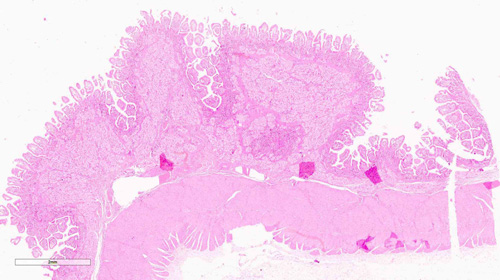

El duodeno se caracteriza por tener las vellosidades (v) de la mucosa (mu) anchas y de altura variable con respecto al yeyuno y al íleon. Entre vellosidad y vellosidad se encuentran las criptas glandulares o de Lieberkün (flechas). En la submucosa (sm) se localizan las glándulas de Brünner. Son glándulas mucosas propias de esta sección de intestino.

Busca las glándulas de Brünner